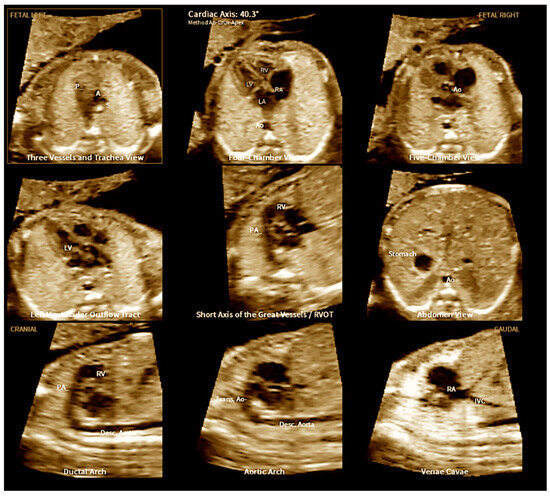

2. Three-Dimensional Ultrasound and Spatio-Temporal Image Correlation

3. Fetal Intelligent Navigation Echocardiography (FINE) and Artificial Intelligence

- Malho, A.; Ximenes, R.S.; Bravo-Valenzuela, N.J.; Araujo Júnior, E. Spatio-Temporal Image Correlation: Three-Dimensional Imaging for Fetal Cardiac Screening and Congenital Heart Disease Assessment. Arq. Bras. Cardiol. 2024, 121, e20230580. [Google Scholar] [CrossRef] [PubMed]

- Magioli Bravo-Valenzuela, N.J.; Malho, A.S.; Nieblas, C.O.; Castro, P.T.; Werner, H.; Araujo Júnior, E. Evolution of Fetal Cardiac Imaging over the Last 20 Years. Diagnostics 2023, 13, 3509. [Google Scholar] [CrossRef]

- Carrillo, M.C.; Rolo, L.C.; Tonni, G.; Araujo Júnior, E. Evaluation of the quality of standard fetal heart views using the FAST, STAR and FINE four-dimensional ultrasound techniques in congenital heart disease screening. Echocardiography 2020, 37, 114–123. [Google Scholar] [CrossRef]